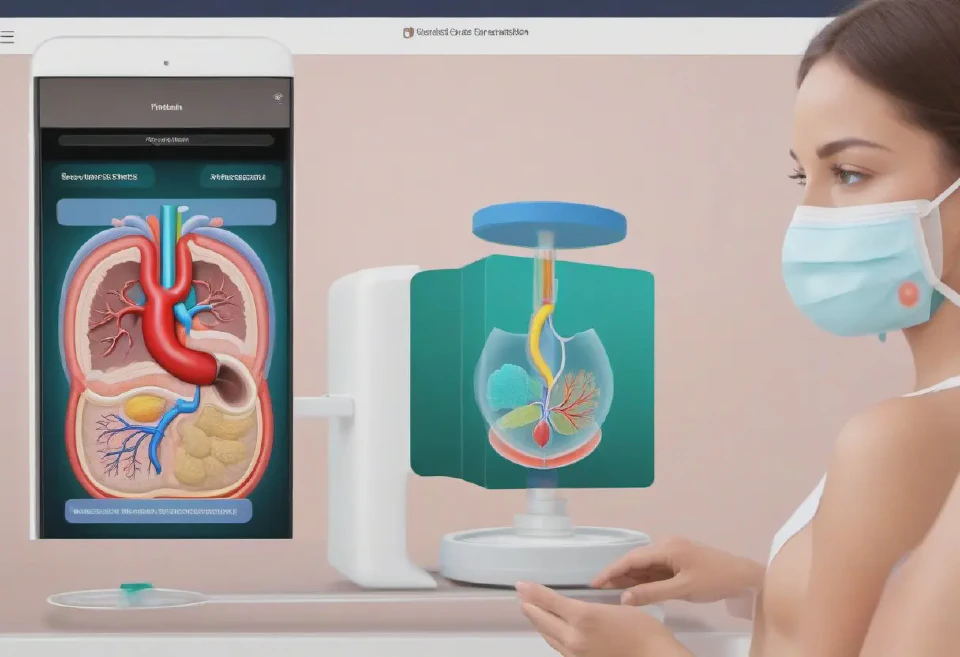

6. A close-up image of a virtual skin scanner tool being applied to a 3D face model, with colorful heat maps indicating areas of skin damage or aging.